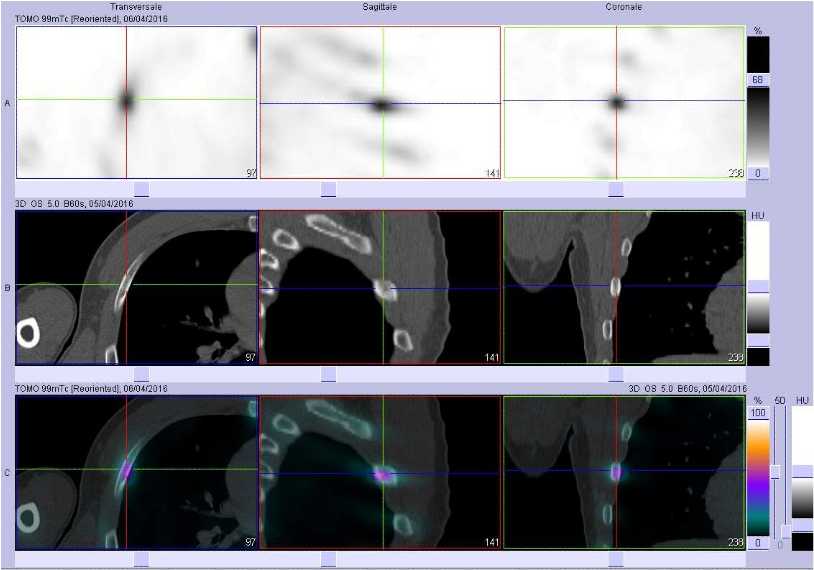

Sur ces coupes TEMP/TDM on observe :

- en haut, un petit foyer d'hyperfixation focalisé sur l'arc axillaire de la 5ème côte droite sur les coupes TEMP.

- au milieu, les coupes TDM semblent montrer une ostéocondensation focalisée de l'arc axillaire de la 5ème côte droite.

- en bas, la fusion des images plaide en faveur d'une ostéite aseptique de l'arc axillaire de la 5ème côte droite.